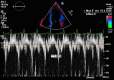

Constrictive pericarditis is a rare cause of right-sided heart failure secondary to a stiff, non-compliant pericardium. Clinical presentation can vary considerably and requires a high suspicion for diagnosis. A 31-year-old male presented to the emergency department with complaints of abdominal distension. An abdominal ultrasound revealed large volume ascites; thus, it was initially suspected he had underlying cirrhosis. However, an echocardiogram revealed a diagnosis of constrictive pericarditis. It's important for clinicians to consider constrictive pericarditis in a patient presenting with unexplained right-sided heart failure.

Keywords: Cardiac MRI; Echocardiography; Pericardial Diseases.